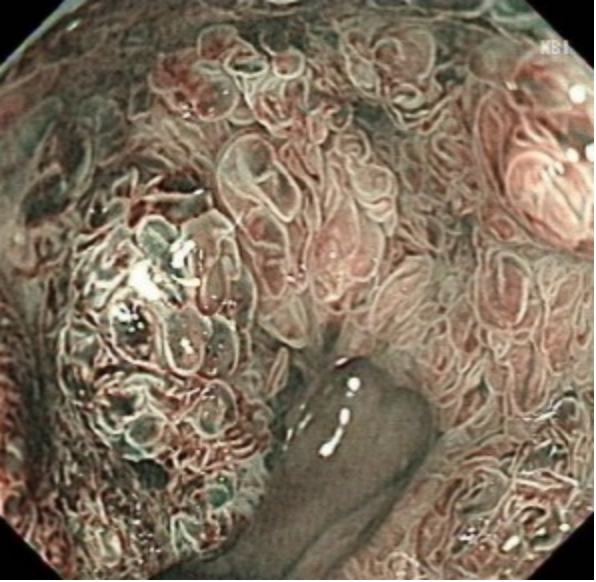

确定是罕见大面积直肠-肛管侧向发育型肿瘤——肿瘤位于肛门齿状线至距离肛门口10cm,而且环周生长,病变肛侧缘已突破肛门齿状线,病变面积大,血管丰富。

▲环周生长的肿瘤